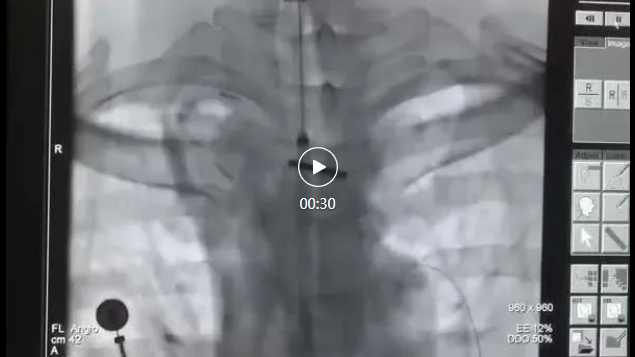

像这位患者因反复咳嗽咳痰,伴胸前区压迫感,在当地医院确诊为肺癌。因邻近食管粘连受侵,形成肿瘤-食管、右侧支气管瘘,气管、右侧支气管局部受压粘连,管腔不均匀变窄,以至于呼吸困难。在我院,我们在DSA引导下在其食管中段狭窄处放置支架,打通生命的“营养快线”。并根据恢复情况,为其实行气管肿瘤射频消融以及支架植入手术,缓解气管阻塞、呼吸困难的症状。术后患者表示,“呼吸畅通,饮食顺畅的感觉简直太好了。”

其中,支架置入是指通过导管将支架送至气管内的狭窄部位,张开后起到支撑管壁,维持气道通畅的作用,从而达到改善呼吸功能的目的,主要针对恶性肿瘤引起的气管支气管狭窄进行姑息治疗,以迅速解除患者呼吸困难的症状,为后续治疗创造条件和机会。

我们介入科团队在这方面有成熟和丰富的诊疗经验。术中麻醉医生全程配合,支气管镜联合DSA在恶性气道狭窄中的活检、吸痰、止血、冷热消融及支架置入,技术成功率100%,安全且疗效满意,为患者点亮生命之光。